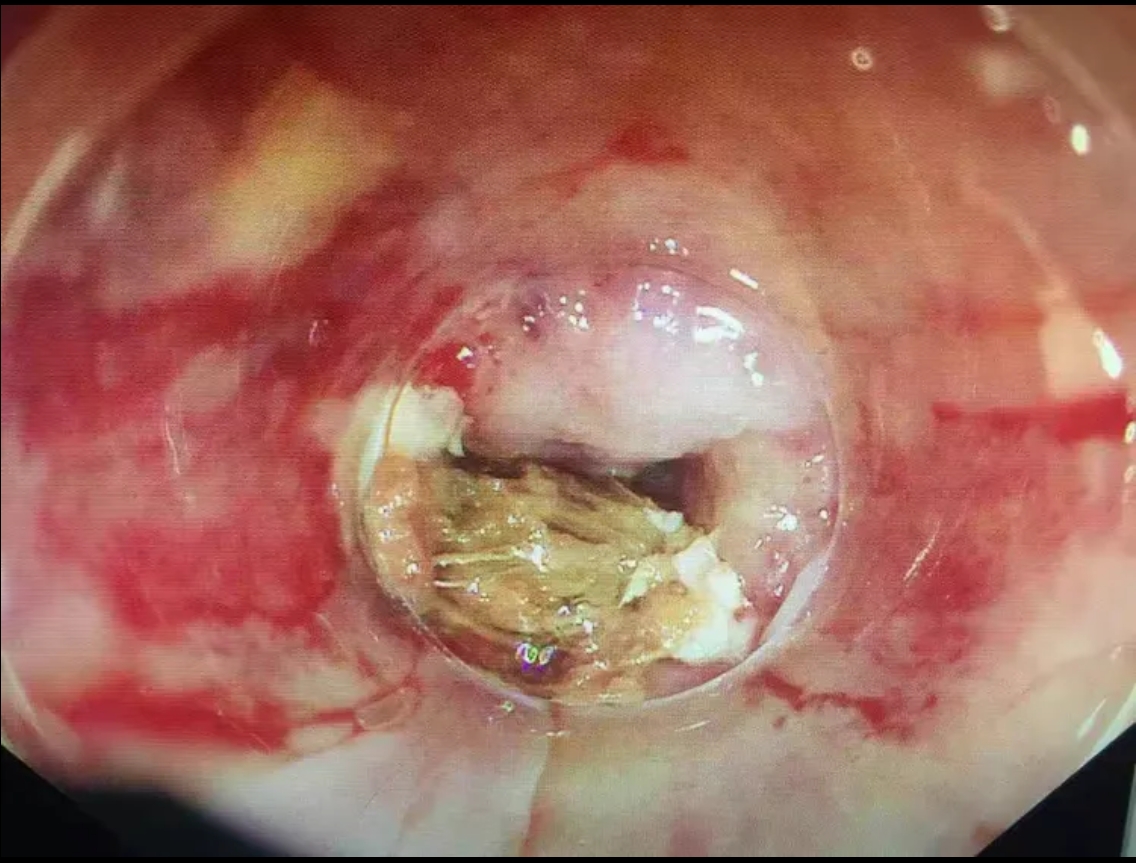

第二步:立即就醫(yī)內(nèi)鏡中心是首選??捎秒娮游哥R直觀地發(fā)現(xiàn)并取出食道的異物。

特別警告:紐扣電池是“頭號(hào)殺手”!如果懷疑兒童吞食了紐扣電池,必須爭分奪秒送往醫(yī)院。電池會(huì)在濕潤的食道內(nèi)泄漏強(qiáng)堿性物質(zhì),短短幾小時(shí)內(nèi)就能造成食道嚴(yán)重?zé)齻?、穿孔,后果不堪設(shè)想。

尖銳異物: 魚刺、雞骨頭、假牙等